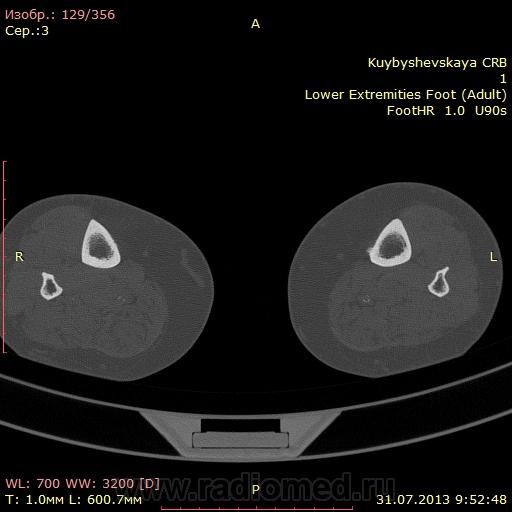

женщина. 69 лет. жалобы на боли в нижней трети голени слева в течении месяца. по снимкам врач написал периостит(к сожалению фотоаппарата нет под рукой)В ближайшее время травм не было. мне досталась только карточка. Пациента не видел. Помогите с диагностикой. вроде бы на зло не похоже. или ошибаюсь?

На зло непохоже, нет мягкоткотканного компонета. Передне-медиальная поверхность голени - самое место для травмы. Только термин "периостит" мне тоже не нравится, написал бы - локальное обызвествления мягких тканей, вероятнее всего посттравматического характера.

По снимкам описал бы как обызвествившуюся гематому, а по КТ больше тянет на экзостоз, только основание очень широкое.

Тем более не "зло". На боковом снимке, в захваченной стопе, р-признаки синдрома переднего большеберцово-таранного соударения. Она же стопа "футболиста" или спортсмена

Может "...в ближайшее время травм И не было...", но что его, наверняка, когда-то "подковывали" бутсой по передней поверхности голени, несомненно.